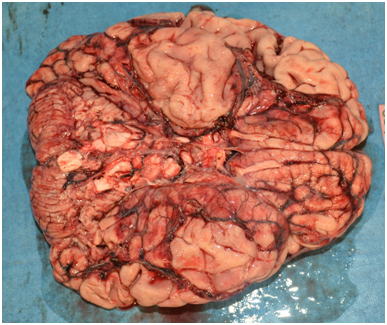

Routine dissection of all organs was done during internal examination. The brain weighed 1400g. It was dusky red in colour with marked congestion and features of meningitis. Cut sections revealed areas of necrosis with clear demarcation of grey and white matter (Figure 2). His neck structures were unremarkable. The lungs were congested and beefy red in colour, the right lung weighing 360g and the left lung 350g. No features of pulmonary embolism were evident to the naked eye. The pleural cavities contained blood-stained serous fluid, 160 ml and 200ml respectively on the left and the right sides. The pericardium contained 75ml of purulent fluid with dense adhesions to the outer surface of the heart (Figure 3). The heart weighed 360g. Major coronary arteries and their principal branches were not calcified and the maximum atherosclerotic narrowing was 30%. The heart valves appeared unremarkable.

The endocardium appeared normal and the myocardium was flabby and pale. The epicardium was covered with yellowish, shaggy fibrous exudate. The undersurface of the diaphragm overlying the surface of the liver too was covered with a thick layer of frank pus. The peritoneal cavity contained approximately 350ml of sero-purulent fluid with offensive smell. Approximately a half of the left lobe of the liver was surgically resected. Pancreaticojejunal, hepaticojejunal, gastrojejunal and jejunojejunal anastomosing sites were free of features suggestive of leakage. A thin yellow purulent exudate was seen over entire peritoneal surfaces. Remaining segments of the small intestinal serosa was congested and flakes of pus were seen adhered onto the surface. No internal hemorrhages were noticed. The large intestinal serosa was also congested and was covered with a thick layer of pus. Both kidneys were normal in size and shape but pale in colour with no visible cortico-medullary demarcation. The bladder contained small amount of cloudy urine with an offensive smell. The bladder mucosa was not shiny and was covered with a thin layer of pus. The mucosa of the ureters too had the same appearance. The remaining portion of the pancreas did not show any overt macroscopic features of acute or chronic pancreatitis. The spleen was enlarged, soft and flabby with a thin layer of pus on the outer surface. It weighed 230g (Figure 4). The histopathology confirmed the gross changes seen and some micrographs are shown here Figures 5 A‒D.